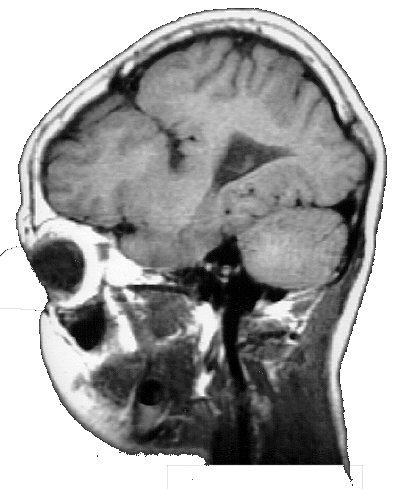

As crianças ARM e KTG são portadoras de lesões cerebrais denominadas Esquizencefalia (Fig. 5 e 6), que são decorrentes de distúrbios no processo embriogênico, que ocorrem no primeiro trimestre da gravidez. As lesões no indivíduo ARM se localizam no lobo frontal esquerdo e incluem também a ausência do septo pelúcido. Já a criança KTG tem as lesões localizadas no lobo parietal direito e também mostra sinais de comprometimento do hipocampo direito.

As lesões do indivíduo WA são do tipo Leucomalácia Multicística e se localizam principalmente no lobo parietal esquerdo. As lesões decorreram de problemas anóxicos perinatais, causados por problemas que a mãe experimentou alguns dias antes do parto. WA e ARM são canhotos e hemiplégicos à direita, e apresentaram atraso no desenvolvimento psicomotor. KTG é destra e tem hemiplegia à esquerda, apresentou também, atraso do desenvolvimento psicomotor.

Os MAREs de todos os indivíduos mostram uma atividade cerebral coerente com a lesão encontrada nas correspondentes MRIs. Assim, por exemplo, ARM tem uma lesão frontal esquerda na MRI, que está associada á um silêncio funcional nas derivações frontais esquerda nos seus MAREs (Fig. 5). Já o indivíduo WA tem uma lesão que se localiza predominantemente no lobo parietal esquerdo, que está associada a uma ausência de atividade nas derivações C3 e P3 nos seus MAREs mostrados na fig. 5. Finalmente, a lesão de KTG se localiza principalmente no lobo parietal direito, que se reflete nos correspondentes MAREs, por uma diminuição da ativação, principalmente, nas derivações P4 e T6.

O quadro eletroencefalográfico de KTG associado ao processamento verbal é totalmente distinto daqueles registrados nos indivíduos ARM e WA. Aqui observa-se uma ativação maior nas derivações F7, T3 e C3, no hemisfério esquerdo, durante as primeiras frases das charadas. Esta atividade se reduz um pouco na fase final da charada. Durante as duas etapas observa-se uma ativação de áreas frontais direitas, mas nunca das regiões temporoparietais do hemisfério direito.

As lesões de KTG se restringem ao hemisfério direito. Nesse caso, a participação do hemisfério esquerdo no processamento verbal fica claramente demonstrada nos MAREs apresentados na fig. 6. KTG é capaz de uma boa compreensão da linguagem, como demonstra seu bom rendimento nos jogos de linguagem. A pobreza de seu uso da linguagem expressiva está relacionado ao sua deficiência mental. Aliás, a inclusão de KTG nesse trabalho tem por finalidade apresentar um padrão de comparação para as crianças ARM e WA, também portadoras de deficiência mental. Dessa maneira, pode-se ressaltar que a plasticidade neural é a responsável pela capacidade de linguagem nessas duas crianças, e que a eventual pobreza do uso da linguagem que elas fazem, está mais associada à uma menor capacidade de processamento cerebral, devido à sua deficiência mental, do que às lesão específicas das áreas verbais do hemisfério esquerdo.